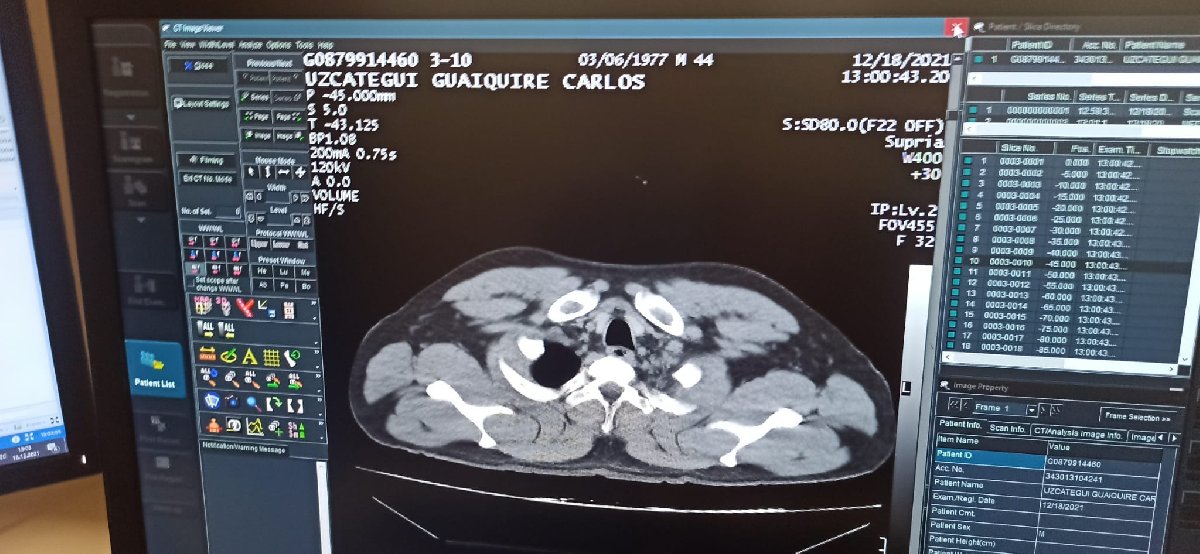

Yapılan ilk muayenenin ardından C.M.U.G., tedavisi için havalimanı emniyet şube müdürlüğü ekiplerinin kontrolünde hastaneye kaldırıldı. C.M.U.G'un hastanede yapılan tomografi kontrolünde mide ve bağırsaklarında 12 adet kapsül kokain tespit edilmesini üzerine, ameliyata alındı.